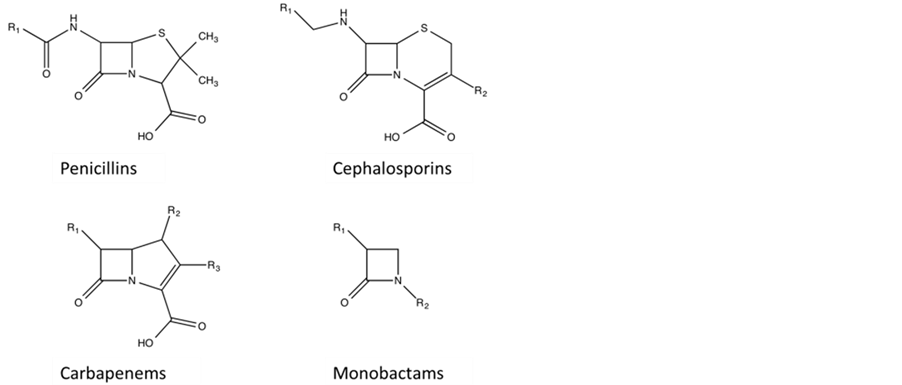

β-lactamases are a family of enzymes that hydrolyse and thus linearise the β-lactam moiety of most of the com- monly used antibiotics, examples of which are shown in Figure 1 [1] . Based on sequence similarity, the

Figure 1 . Chemical Structure of representative antibiotics types containing signature beta lactam ring. The R groups indicate modifications to the core structure of the respective antibiotics.

β-lactamases are subdivided into four groups, A, B, C and D [2] [3] . Subgroups A, C and D are serine-β-lacta- mases SBLs; they employ a serine residue in their active site to initiate hydrolysis of β-lactam substrates and do not require metal ions for their function [2] -[5] . SBLs have been extensively studied and their threat to human health is, at least currently, under control, as clinically useful SBL inhibitors such as clavulanic acid can be co-administered with the antibiotics to maintain their antibacterial effect [4] [5] . In contrast, no such inhibitors are currently available for B-type β-lactamases, termed MBLs. In addition, their threat to human health is further exacerbated by their ability to spread easily between species, mainly through horizontal gene transfer [6] [7] . MBL-encoding genes can be part of either the chromosomal framework of the bacterial species, as observed for instance in Pseudomonas aeruginosa [8] , or are located on mobile genetic elements that can easily be shared among species via horizontal gene transfer (examples include P. aeruginosa, Klebsiella pneumonia and Acine- tobacter baumannii [9] -[11] ). This facile transfer of genetic information amongst pathogenic bacteria, in com- bination with increasing global travel capabilities of the human population provides an ideal framework for the rapid spread of antibiotic resistance [10] .